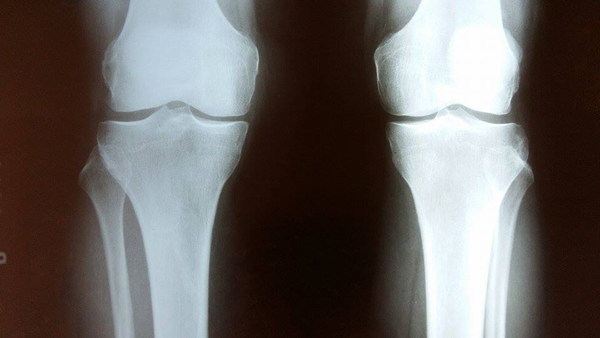

Деформирующие остеоартрозы коленных суставов являются актуальной проблемой современной медицины. Остеоартроз коленных суставов поражает как костную структуру, так и хрящи и окружающие мягкотканные составляющие коленного сустава. При запущенных стадиях остеоартрозов показано эндопротезирование. Нижепредставленный метод применяется при начальных стадиях остеоартроза с варусной деформацией суставов.

02.03.2015г. в отделение ортопедии больной Г.Г., 1957г. рожд, врачом-ортопедом Грачья Арутюняном была произведена операция по коррекции варусной деформации коленного сустава. Суть метода заключается в комбинированной операции:

- Артроскопия коленного сустава.

- Высокая вальгизирующая остеотомия большеберцовой кости с фиксацией Т-образной пластиной.

В результате операции были устранены внутрисуставные повреждения и исправлена ось конечности, что позволило приостановить дальнейшее развитие остеартроза у больной.

Особенность вышеописанной операции- замедлить развитие остеоартроза, исправить ось конечности с целью предотвращения в дальнейшем более объемных оперативных вмешательств.

Метод комбинированного оперативного вмешательства по лечению варусной деформации коленного сустава успешно применяется в мц “Эребуни” в последние 5 лет и имеет прекрасные результаты.